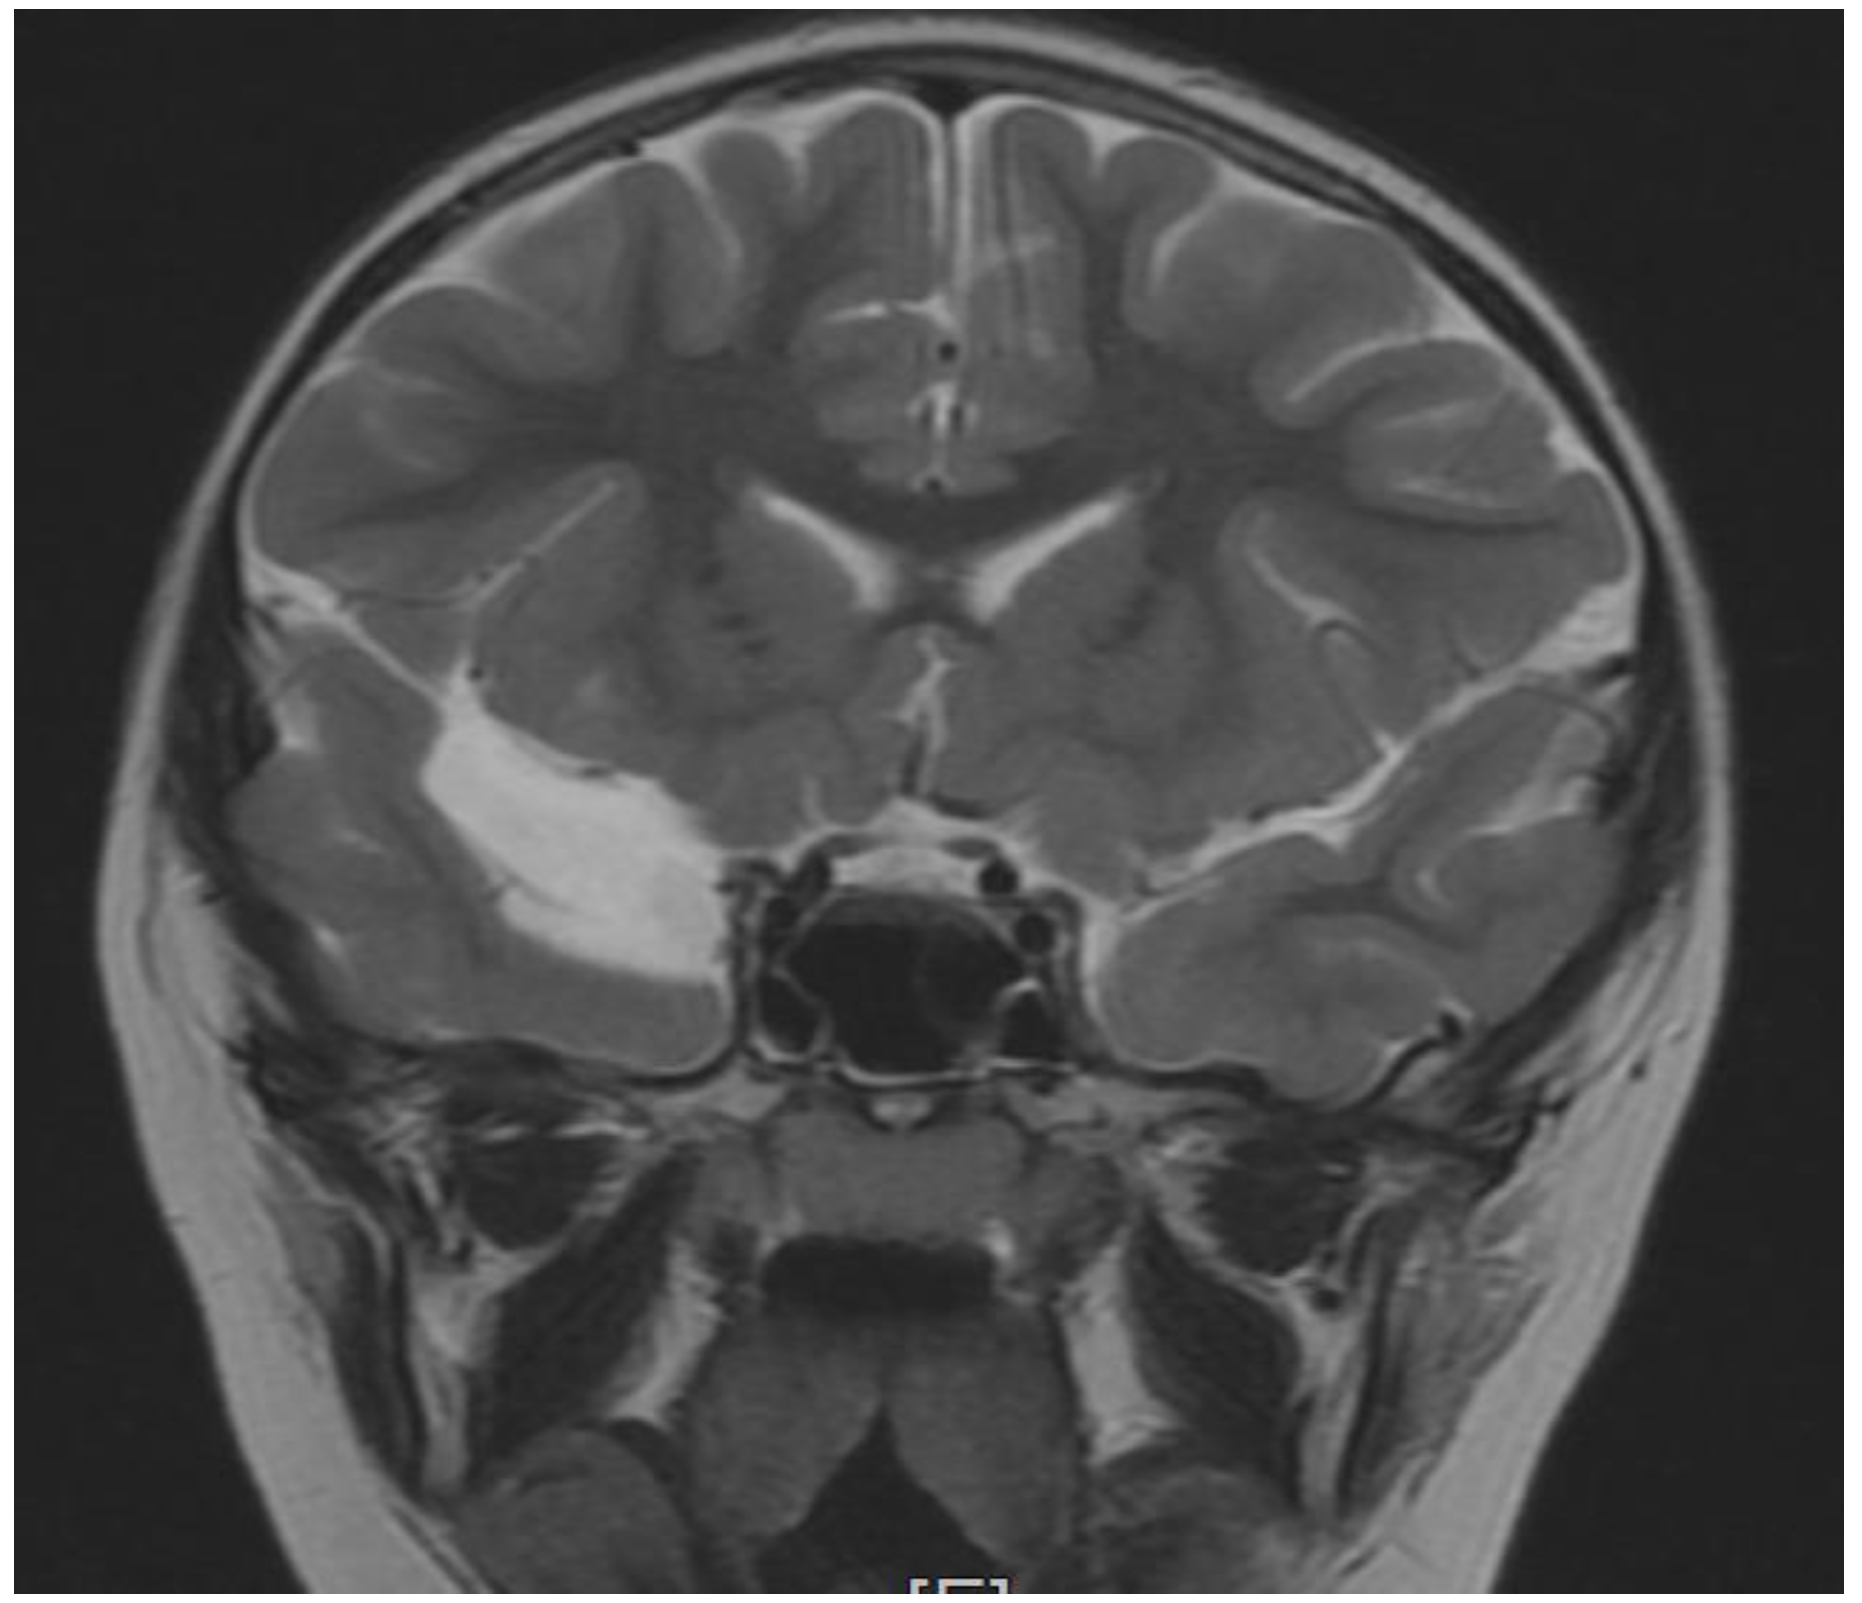

| Brain MRI | |

| yes | Changes in temporal lobe- cyst |